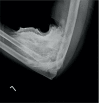

Methods: Two cases were compared in the context of the prevailing literature. One of these was a large volume extravasation of an iodine-based imaging contrast agent with a diffuse distribution pattern, rendering it unsuitable for this method of evacuation. This is contrasted with a case with a more discrete collection better suited to acute evacuation.

Results: This review found that current literature does not account for distribution patterns of extravasation medium in the decision-making process around surgical intervention.

Conclusions: A review of the relevant literature suggests that the pattern of distribution should be accounted for when considering surgical management.